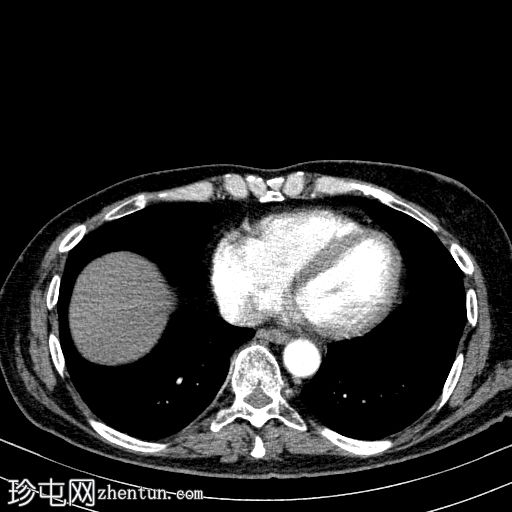

轴向

非造影

胰体尾弥漫性增大,特征为胰腺实质低强化,无明显坏死区域。

该病灶与以下表现相关:

胰周筋膜平面边界不清的污迹,无明显壁形成、气室、固体碎片或血液产物。

多个亚厘米大小、非特异性的腹主动脉旁淋巴结和肠系膜淋巴结,可能具有反应性。

病变范围如下:

病变横向延伸至左前肾旁间隙,伴有Gerota筋膜增厚。

病变向下延伸至盆腔。

无肠系膜或脾脏血管阻塞的证据。

未见导管扩张或钙化。

在疾病早期,可能出现胰腺肿大、胰腺组织低增强、胰周脂肪条带、积液和筋膜增厚。